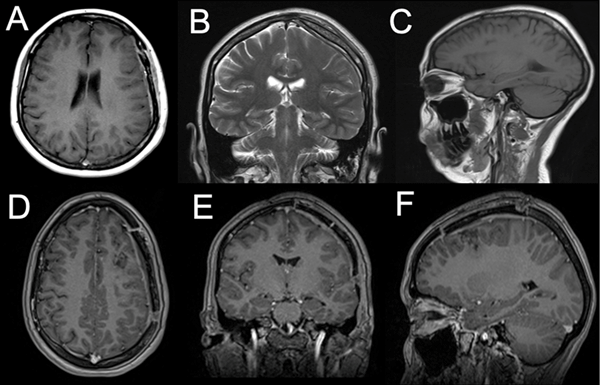

Al examen físico de ingreso se encontraba lúcida sin foco motor ni sensitivo. Como únicos datos positivos, se evidenciaron afasia de expresión, agrafia y alexia. En el estudio de resonancia magnética (RM) cerebral se observó una lesión extraaxial frontal izquierda, de características heterogéneas a predominio hipointenso en secuencia T1 e hiperintensa en T2, sin restricción a la difusión con tenue realce periférico a la administración de contraste endovenoso. Sus mediciones aproximadas eran 5.44 x 4.65 x 5.43 cm. Dicha lesión no producía edema, sin embargo, colapsaba parcialmente el asta frontal del ventrículo ipsilateral y desviaba discretamente las estructuras de línea media hacia el lado contralateral (Figura 1).

Figura 1. Resonancia magnética cerebral prequirúrgica. A) Secuencia axial T1. B) Coronal T2. C) Sagital T1. D-F) Se observa una lesión frontal izquierda redondeada de componente sólido-quístico de aproximadamente 54 mm x 46 mm x 54 mm, de localización extraaxial, que colapsa el ventrículo lateral ipsilateral, con tenue realce a la administración de contraste endovenoso.